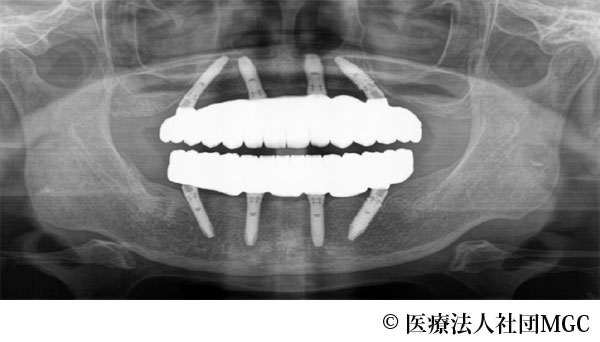

【症例1】上下All-on-4(オールオンフォー)

- 治療前

- 治療後

- 治療名

- 上下All-on-4(オールオンフォー)

- 費用

- 5,915,800円(税込)

- 期間

- 8ヵ月

治療内容

患者様の症状

歯がボロボロで食事が困難であるとご来院されました。

治療法

ご相談の結果、患者様の生活の質(QOL)を向上させ、しっかり噛めるように上下All-on-4(オールオンフォー)を行いました。

治療結果

機能性、審美性ともに改善し、満足していただけました。

※治療結果は患者様によって個人差があります。

治療を行う上での注意点(リスク・副作用)

インプラント周囲炎の可能性、まれに歯が欠ける可能性があります。